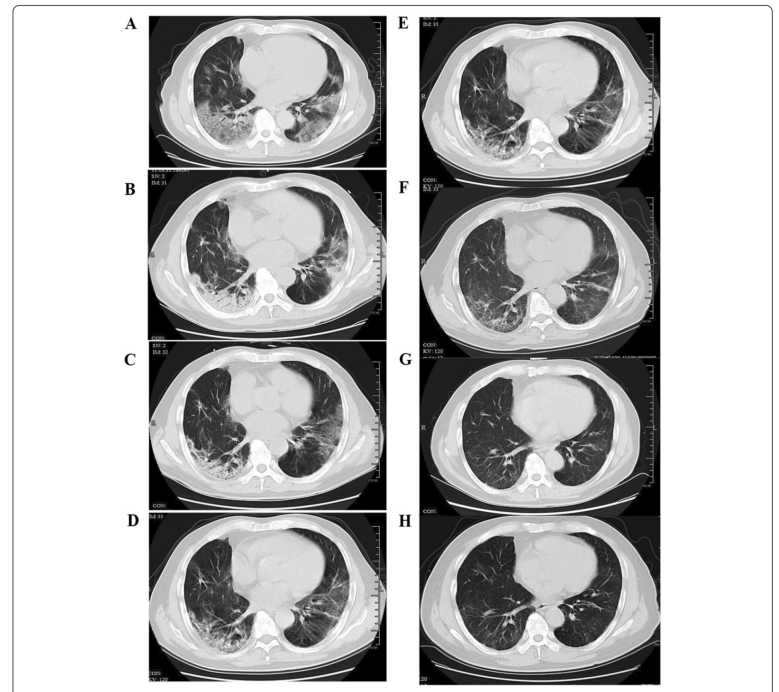

1 Şubat’ta SARS-CoV-2 enfeksiyonu olan, aynı gün hastaneye başvuran ve hastanede yatışı sırasında kortikosteroid ve yüksek akımlı nazal kanül ile oksijen tedavisi verilen hastanın,

A 7. günde elde edilen ve yaygın subplevral GGO’ (buzlu cam opasitesi) yu gösteren bir Tarama.

B Kısmi konsolidasyonlu subplevral GGO’yu gösteren 14. günde elde edilen tarama.

C Hastalığın 21. gününde alınan tarama subplevral GGO ve konsolidasyonun kısmen azaldığını gösteriyor.

D GGO alanlarında gelişen düzensiz lineer opasiteleri gösteren, hastalığın 28. gününde elde edilen tarama.

E Tarama, taburcu olduktan 1 ay sonra (hastalığın 62. günü) düzensiz lineer opasiteler ve subplevral retikülasyon gösteren elde edildi.

F Taburcu olduktan 3 ay sonra (hastalığın 112. günü) alınan subplevral retikülasyon gösteren tarama.

G Taraması taburcu olduktan 6 ay sonra (hastalığın 210. günü) GGO bazında hafif düzensiz lineer opasiteler ve retikülasyon gösteren alanlar elde edilmiştir.

H Tarama, taburcu olduktan 1 yıl sonra (hastalığın 390. günü) ince düzensiz lineer opasiteler ve GGO bazında retikülasyon gösteren tarama.